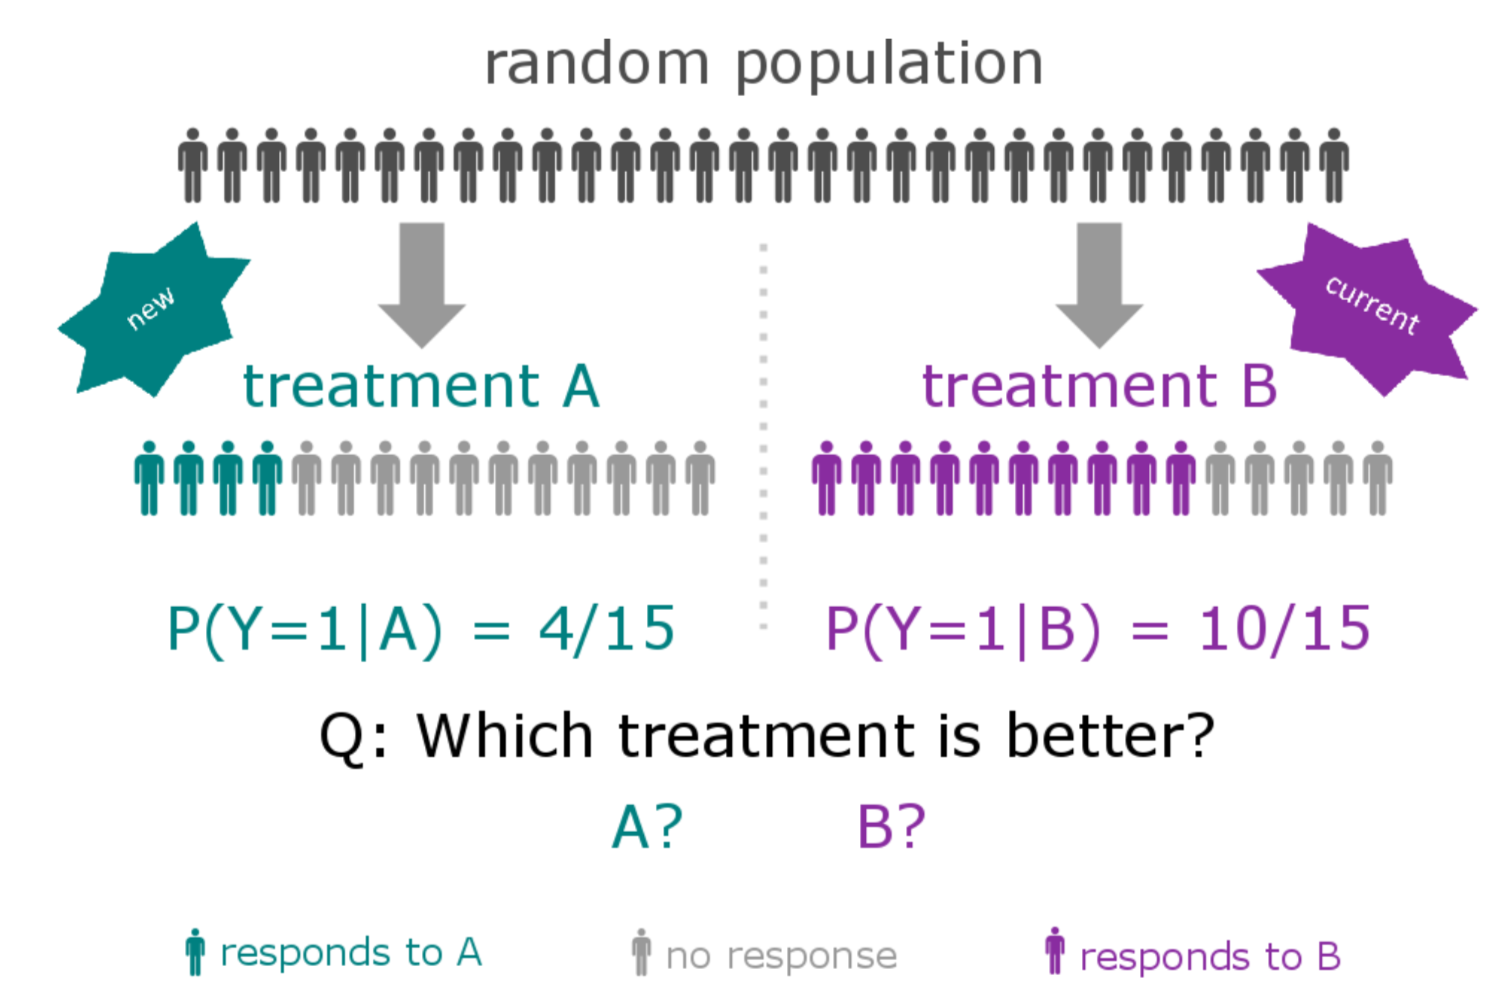

The "old" way of conducting clinical trials

New compound is developed and is thought to deliver a (small) benefit over current therapies for a specific histology

A large number of patients are enrolled (at least hundreds)

The response rate of the treatment population is tested against a control group

Alternative Designs

Often means single arm

Smaller populations

May include multiple histologies

Still work within FDA regulation, often including "all-comers"